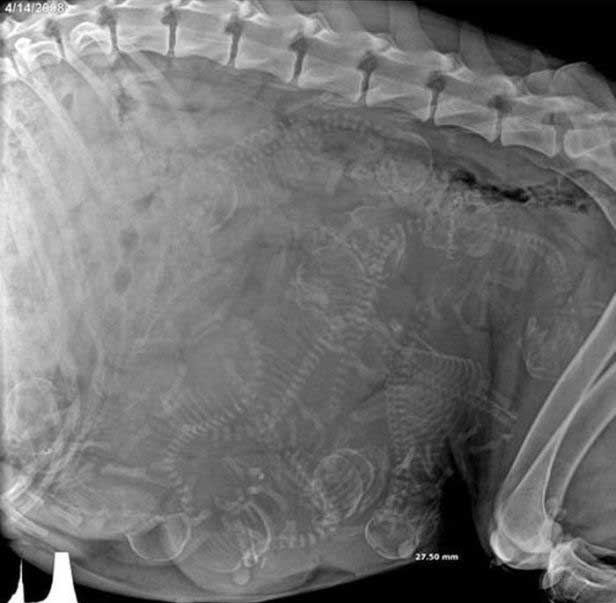

妊娠した様々な動物たちをレントゲン(X線)写真で見てみたギャラリー。サメ、ネズミ、犬、猫など。一度に複数の子供を出産する犬や猫などは特に怖い事に…。

4. イヌ